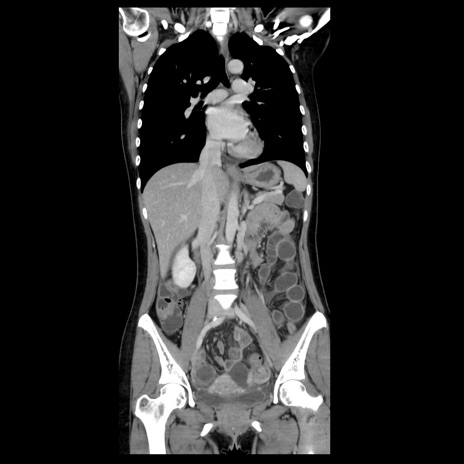

症例39(冠状断像)

【症例】40歳代女性

【主訴】上下腹部痛

【現病歴】2日目から下腹部痛あり。夜間は痛みで眠れなかった。昨日より上腹部痛と下痢が出現。臥位で痛みは軽快したため、休んでいた。本日になって臥位でも立位でも痛みが強くなってきたため救急要請。

【既往歴】子宮内膜症

【身体所見】部:平坦・軟、左上下腹部に圧痛あり、反跳痛あり。

【データ】WBC 21800、CRP 26.78

CT